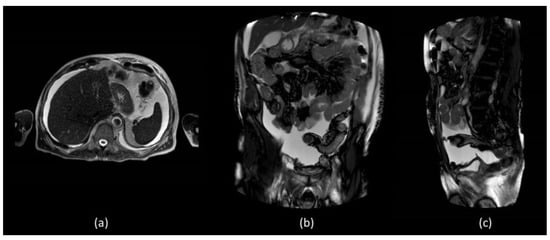

In order to better assess the post-surgery pelvic region, abdominal MR was performed which did not show evidence of surgical injuries and liver diseases (Figure 2).

MR T1 weighted (a) axial section of the liver did not show diseases but confirmed the presence of massive fluid effusion, visible in the supra and submesocholic space and also in the coronal (b) and sagittal images (c).